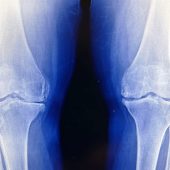

Ученые, возможно, нашли способ, помогающий организму восстановить собственные кости. Важную роль в методе играет рецептор GPR133. Такая терапия может в перспективе изменить подход к лечению остеопороза.